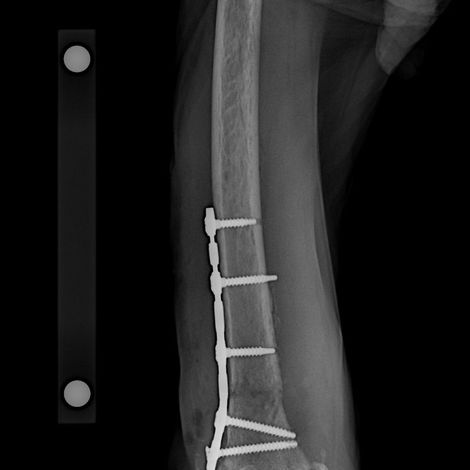

01. Cirugía de Especialidad

- Cirugía oncológica y corrección de defectos cutáneos.